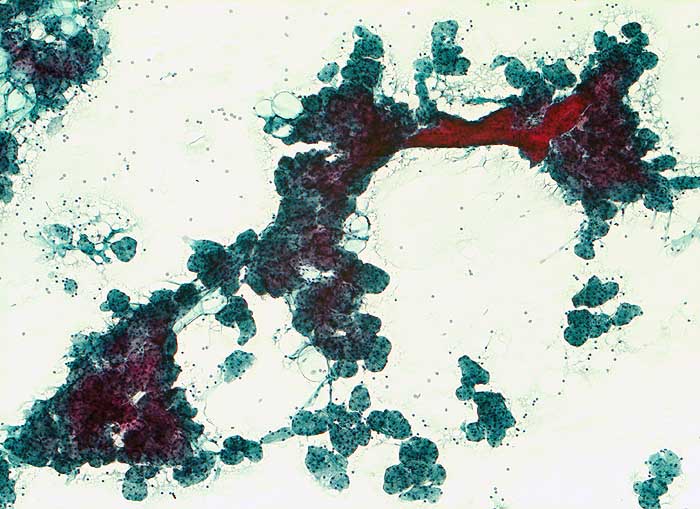

PathoPic – image database / PathoPic ID 5479 - Sialadenose

Sialadenose

Feinnadelpunktion Parotis: hypertrophe runde Drüsenazini mit rotem Schaltstück. Die Azinuszellen sind deutlich vergrössert zytoplasmareich.

Histologie: Chronische obstruktive Sialadenitis mit Fibrose und Atrophie der Drüsenazini

Nicht neoplastische Vergrösserung der Speicheldrüsen. Zytologisch lässt sich die Diagnose aufgrund des klinischen Hintergrundes und des Fehlens neoplastischer oder entzündlicher Veränderungen stellen.